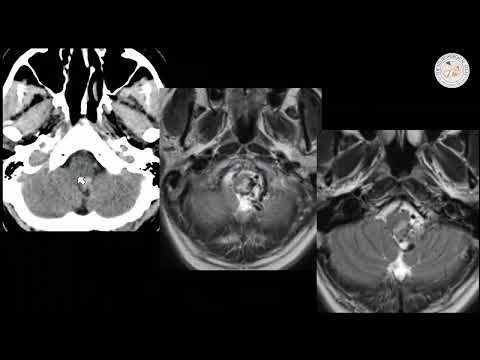

Endovascular treatment of a spinal dural arteriovenous malformation DAVF

Endovascular treatment of a spinal dural arteriovenous malformation (DAVF)